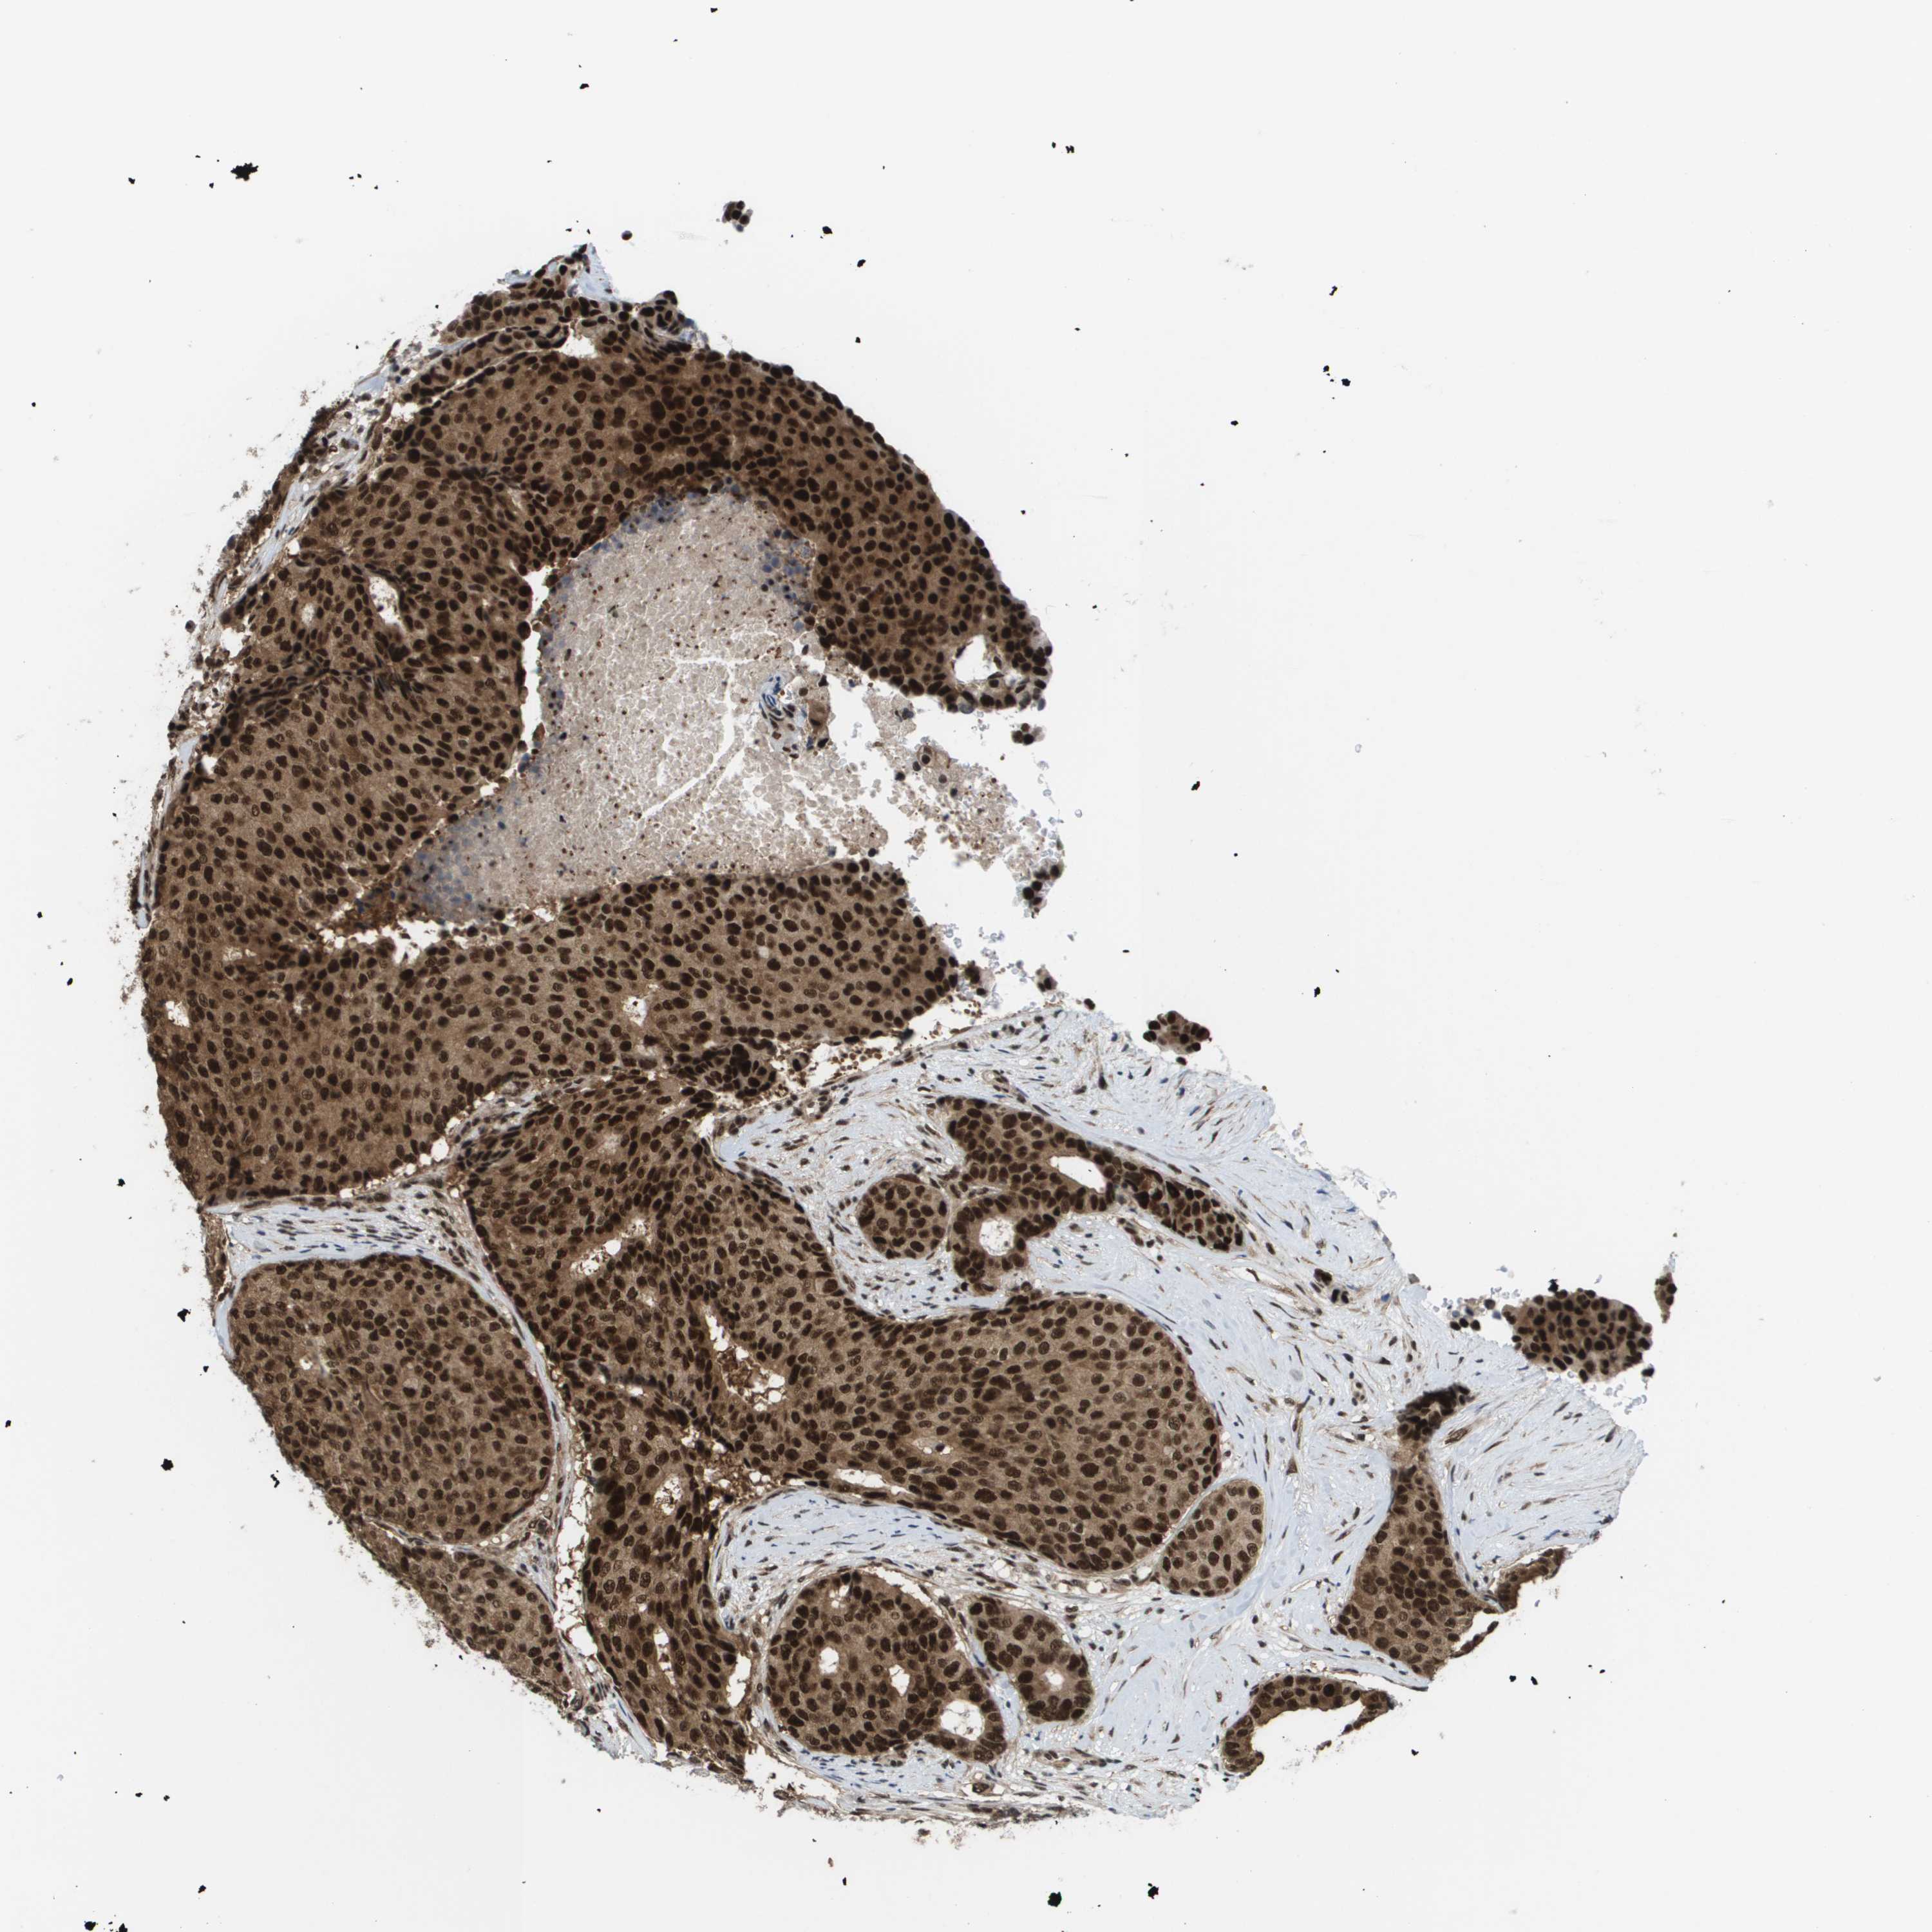

CANCER BREAST CANCER Show tissue menu

BRCA TCGA BRCA VALIDATION PROTEIN EXPRESSION

Breast cancer

Breast invasive carcinoma